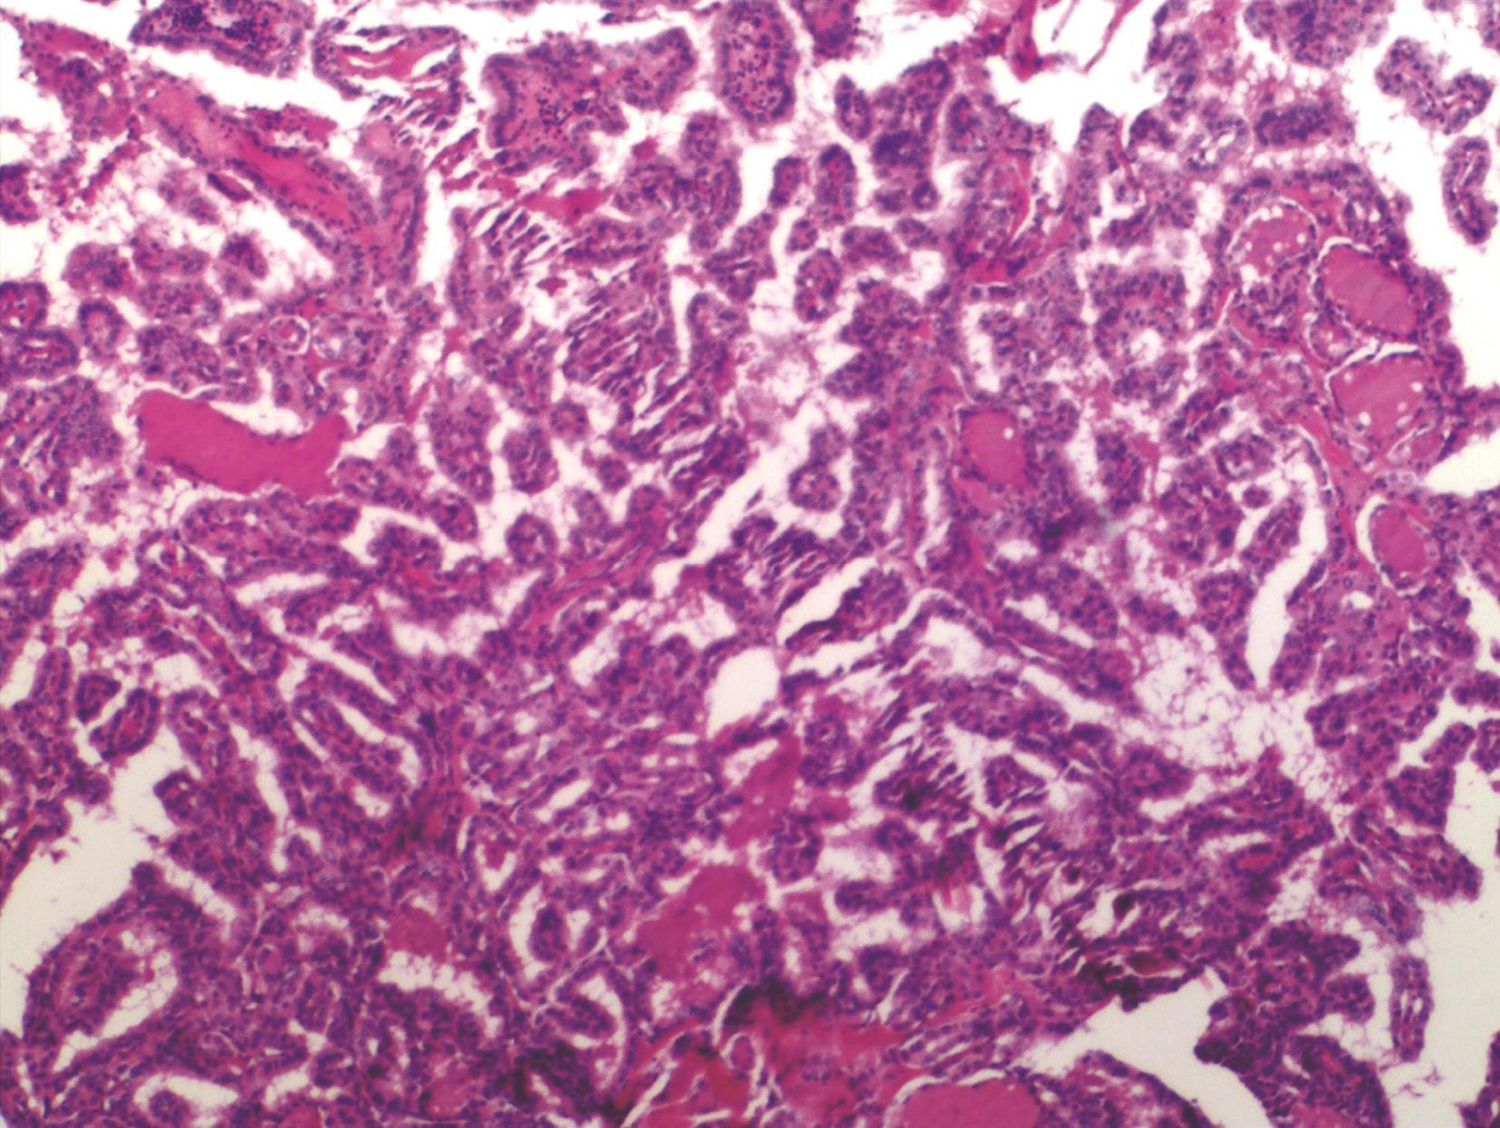

(甲状腺右叶)乳头状癌,最大直径2cm,小灶侵及周围横纹肌组织(图12)。

(甲状腺左叶及峡部)见乳头状癌组织,并侵及周围横纹肌组织。

(皮下包块)见癌组织。

图12 术后病理切片

淋巴结转移癌(5/15)

(1)(右颈Ⅱ区清扫)2/7,另见癌结节3枚。

(2)(右颈Ⅲ区清扫)1/1。

(3)(右颈Ⅳ区清扫)1/1,另见癌结节1枚。

(4)(右颈Ⅴ区清扫)0/5。

(5)(右颈Ⅵ清扫)纤维脂肪组织中未见癌组织。

(6)(左颈Ⅵ清扫)1/1。